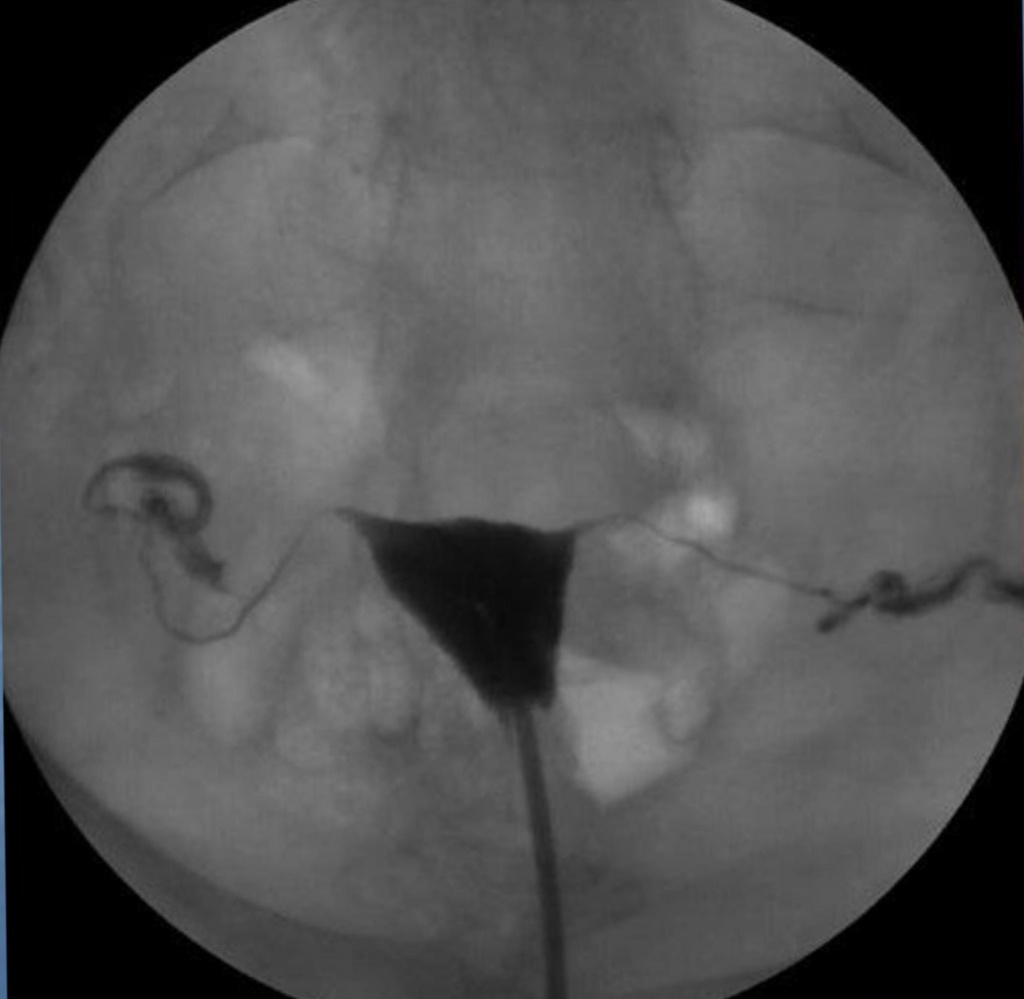

Медицинские снимки: Проходимость маточных труб

Раздел: Кадры-подсказки